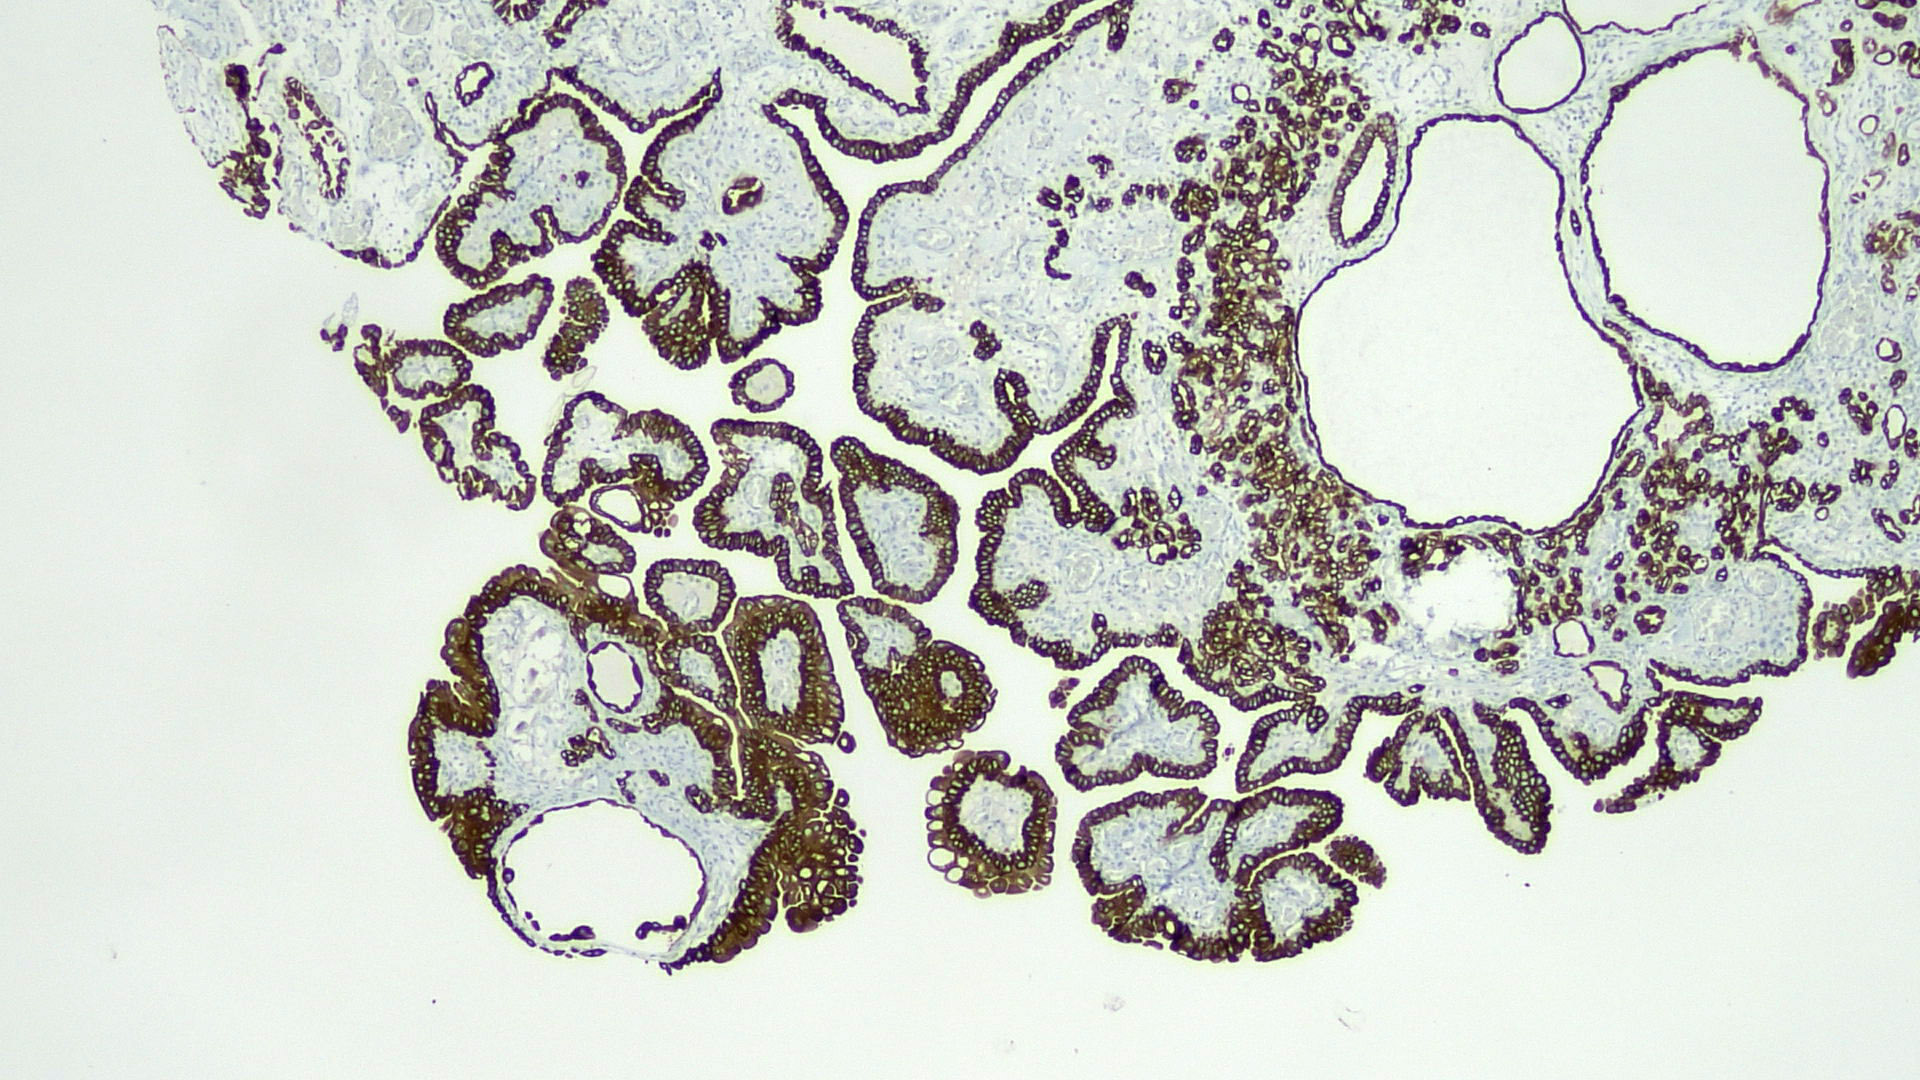

- Tubules lined by simple cuboidal, flattened or hobnail cells, forming an exophytic papillary or endophytic lesion (Urology 2016;95:29)

- Associated acute and chronic inflammation and edema in the stroma; lack of desmoplastic reaction

- Many morphologic variants (multiple patterns may occur in the same cases): papillary, tubular, tubulocystic, polypoid, flat, fibromyxoid, signet ring cell-like (Mod Pathol 2013;26:792)

- Hyaline rim surrounds the tubules (PAS positive thickened basement membrane) (Adv Anat Pathol 2019;26:171)

Microscopic (histologic) images